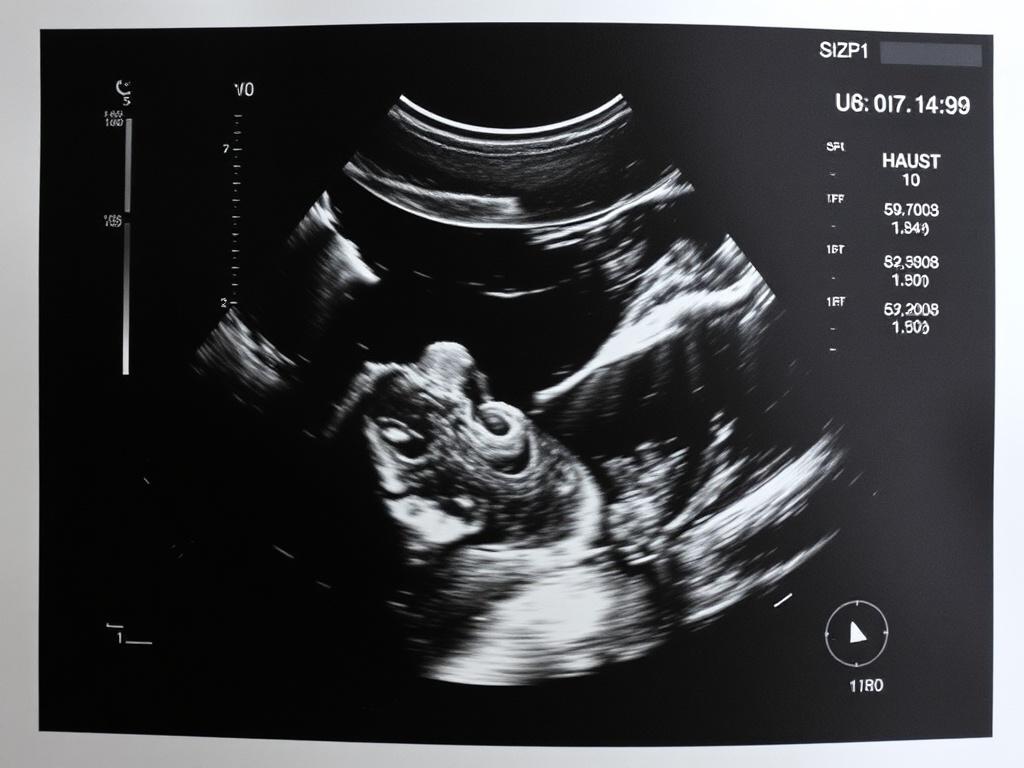

Ультразвуковое исследование — это метод визуализации внутренних органов с помощью высокочастотных звуковых волн. Врач с помощью датчика получает изображение на экране и фиксирует изменения в структуре тканей. Процедура неинвазивная, не вызывает боли и подходит для повторных обследований.

Назначают УЗИ при самых разных ситуациях: для контроля хронических заболеваний, при появлении боли или подозрении на патологию, в динамическом наблюдении во время лечения и при беременности. Часто оно становится первым шагом для понимания, есть ли повод для дальнейших обследований.

- УЗИ при беременности: следуйте инструкциям женской консультации — для ранних сроков может потребоваться полный мочевой пузырь.

- Можно ли делать УЗИ беременным? Да, ультразвук безопасен и широко применяется в акушерстве.